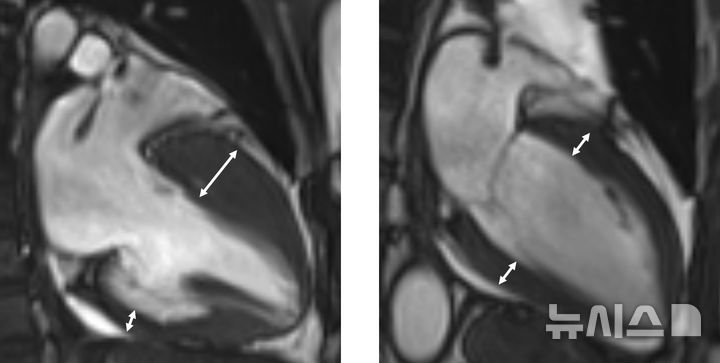

진단은 심장초음파, 자기공명영상 등 영상검사를 통해 이뤄지며, 비후된 심근 내에 섬유화가 진행돼 있거나, 근육조직이 지방조직으로 변성이 돼 있는 상태가 관찰된다. 하지만 이 같은 조직변성이 없는 비후성 심근병증도 있는 만큼 전문의의 종합적 판단이 중요하다.